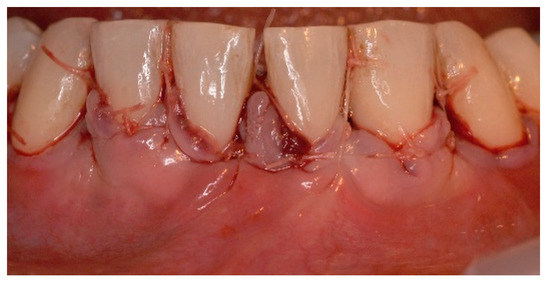

5. Materials and Methods

6. Results